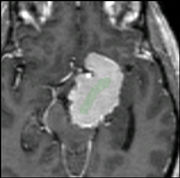

Grow Cut Segmentation is a competitive region growing algorithm using cellular automata. The algorithm works by using a set of user input scribbles for foreground and background. For N-class segmentation, the algorithm requires a set of scribbles corresponding the N classes and a scribble for a don't care class. The algorithm executes as follows:

• Using the "user input scribbles", the algorithm automatically computes a region of interest that encompass the scribbles.

• Next, the algorithm iteratively tries to label all the pixels in the image using the label of pixels in the user scribbled portions of the image.

• The algorithm converges when all the pixels in the ROI are labeled, and no pixel can change it's label any more.

• Individual pixels are labeled by computing a weighted similarity metric of a pixel with all its neighbors, where the weights correspond to the neighboring pixel's strength. The neighbor that results in the largest weight greater than the given pixel's strength, confers its label to the given pixel.

After the segmentation, the user can edit the segmentation by providing additional gestures in the image as illustrated in the figure below.

Additional edits added to the existing segmentation

Final segmentation

The segmentation resulting from the user's edit is also shown.